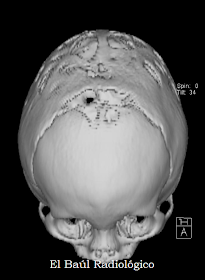

Esta exploración de Tomografía Computarizada fue solicitada por la sospecha clínica de craneosinostosis frontal y sagital. Por eso se realizó una adquisición helicoidal preliminar para poder realizar reconstrucciones volumétricas de superficie (SSD). En las siguientes imágenes (Figuras 14, 15 y 16) se puede apreciar con nitidez, los defectos de osificación tan llamativos de los huesos de la bóveda craneal.

FIGURA 14)

FIGURA 15)

FIGURA 16)